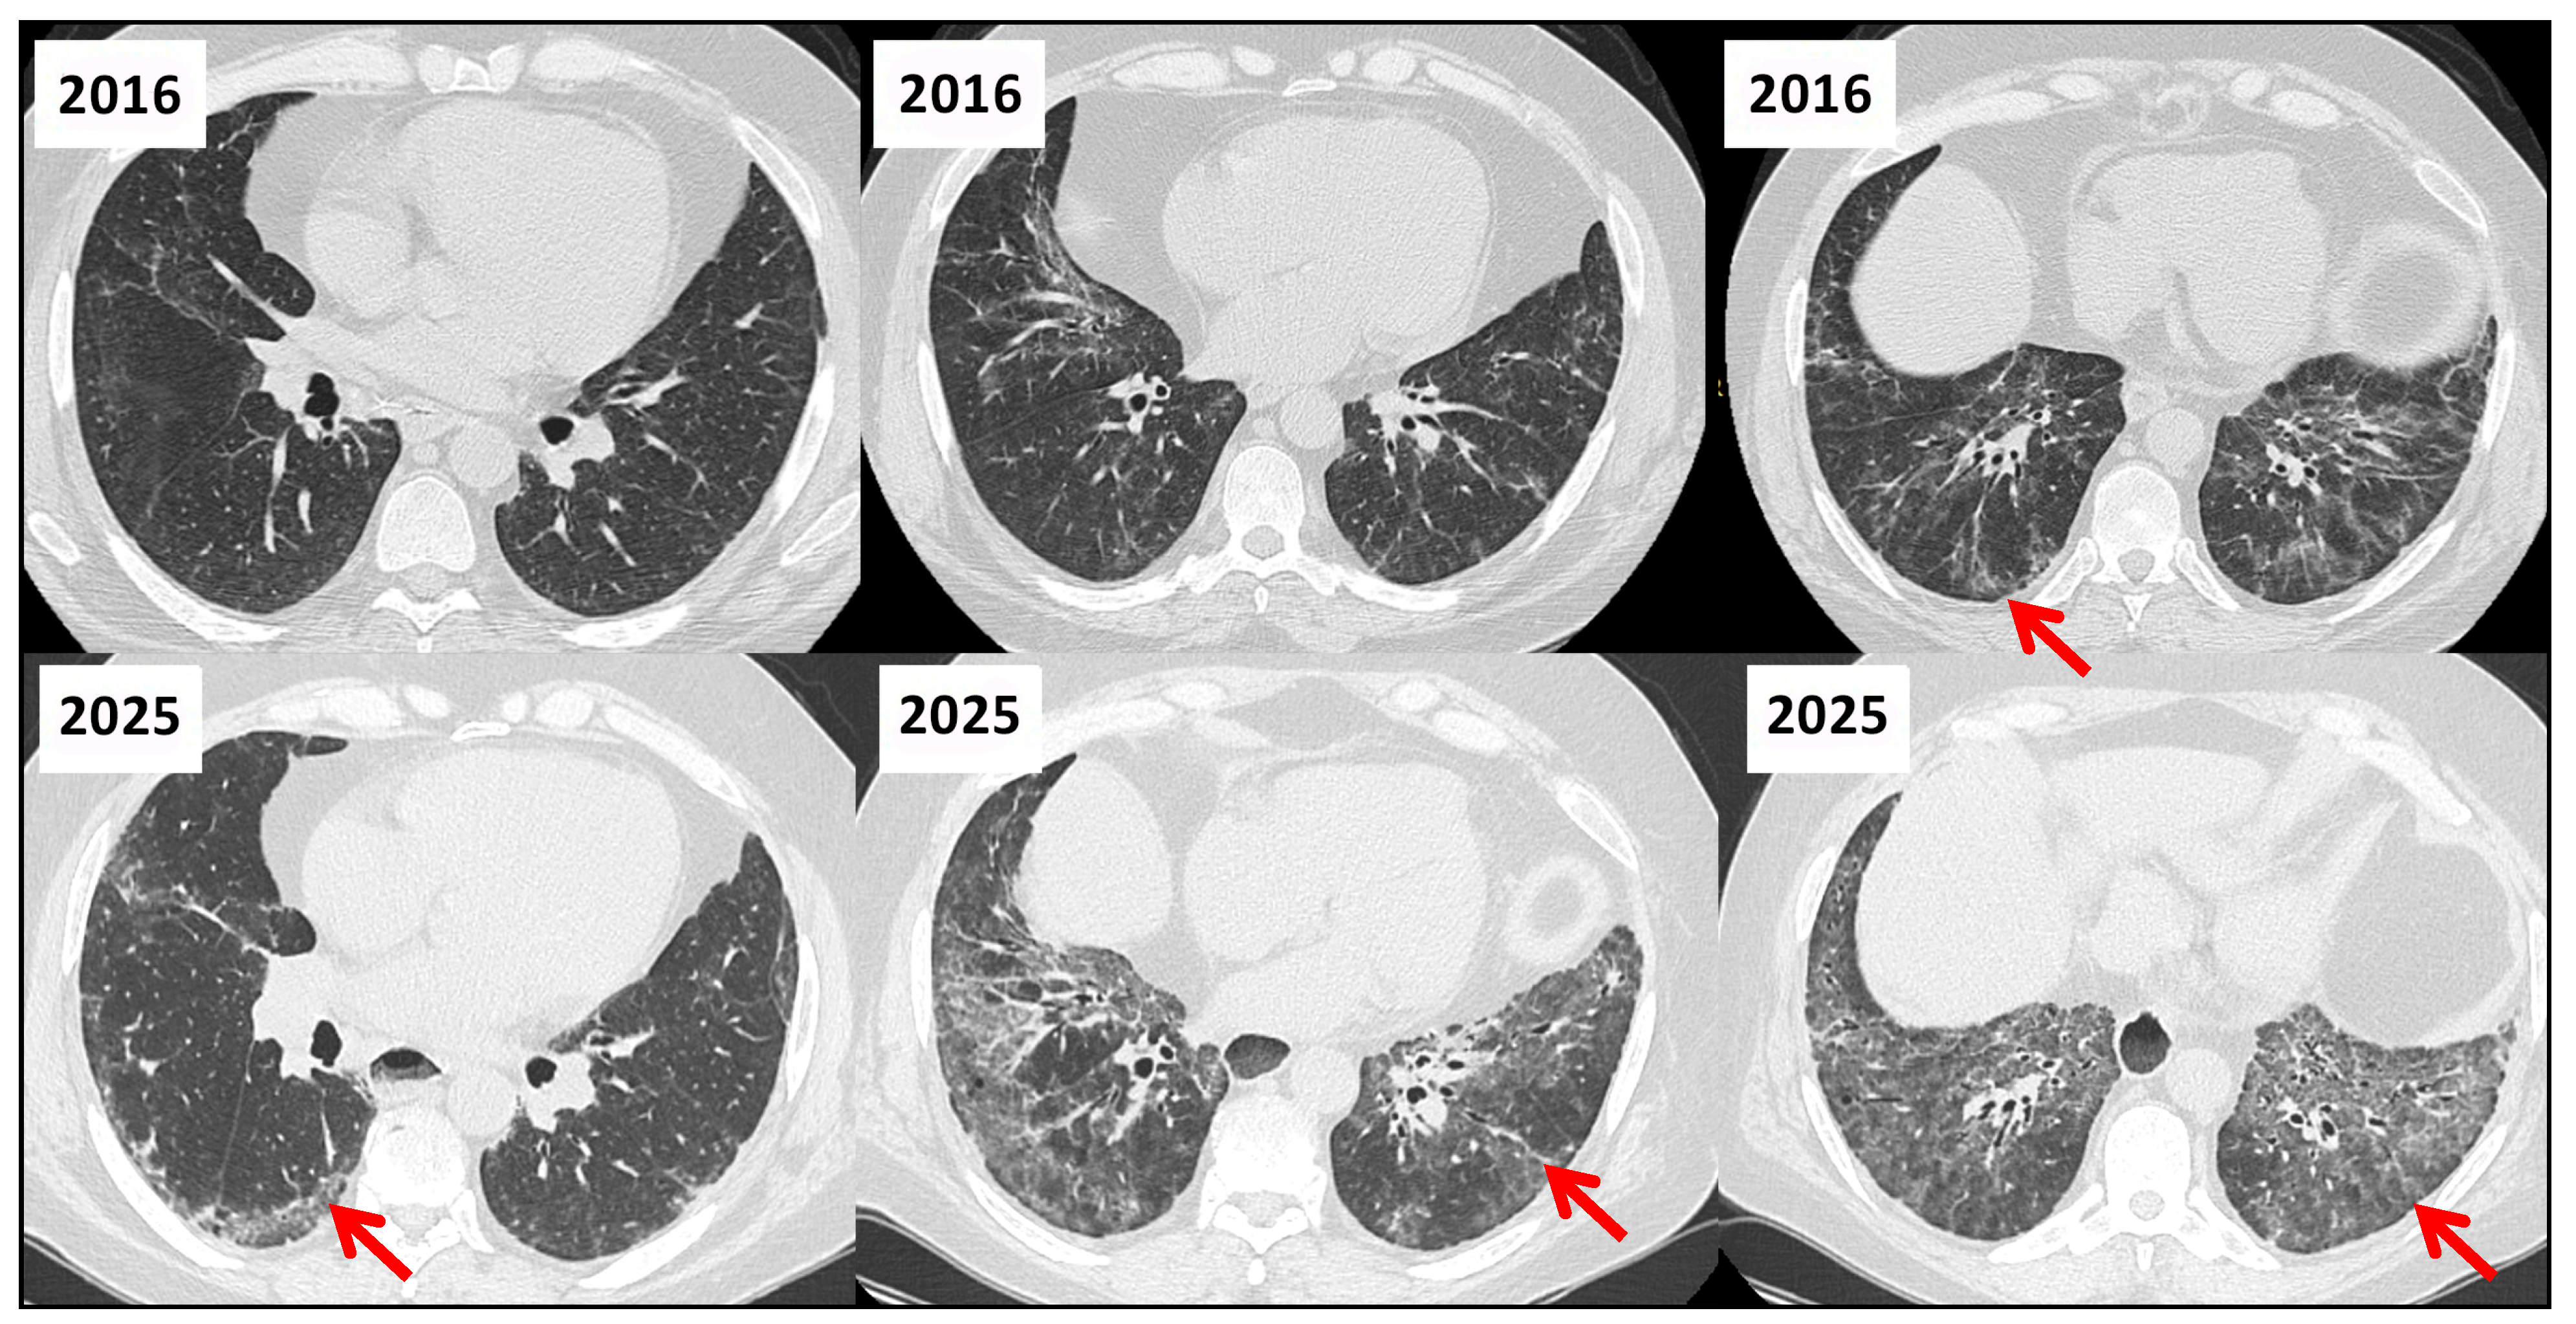

3.5. Role of HRCT in Longitudinal Assessment of CTD-ILD

| HRCT Patterns | - UIP is the most common pattern (~40–60%)—strong negative prognostic marker - NSIP (~15–25%) - OP and mixed types less frequent. (<20%)  | [43] |

| Distinctive HRCT Signs | - Anterior upper lobe (AUL) sign  - Straight-edge (SE) sign - Exuberant honeycombing (EHC)  | [45] |